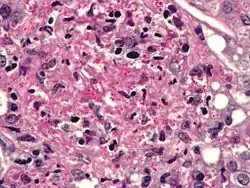

Infecting C. neoformans cells are usually phagocytosed by alveolar macrophages in the lung.[11] The invading C. neoformans cells may be killed by the release of oxidative and nitrosative molecules by these macrophages.[12] However some C. neoformans cells may survive within the macrophages.[11] The ability of the pathogen to survive within the macrophages probably determines latency of the disease, dissemination and resistance to antifungal agents. In order to survive in the hostile intracellular environment of the macrophage, one of the responses of C. neoformans is to upregulate genes employed in responses to oxidative stress.[11]